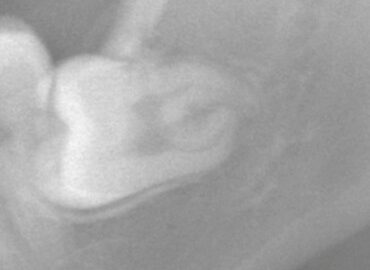

- 2024/09/30 永久歯が出てこない理由

こんにちは、静岡市駿河区にある歯科医院、小嶋デンタルクリニックです。 子供の交換期において、乳歯が脱落して永久歯がすぐ萌出してくるという形は至って正常です。 しかし乳歯が抜けたのに永久歯が出て … 続きを読む 永久歯が出てこない理由